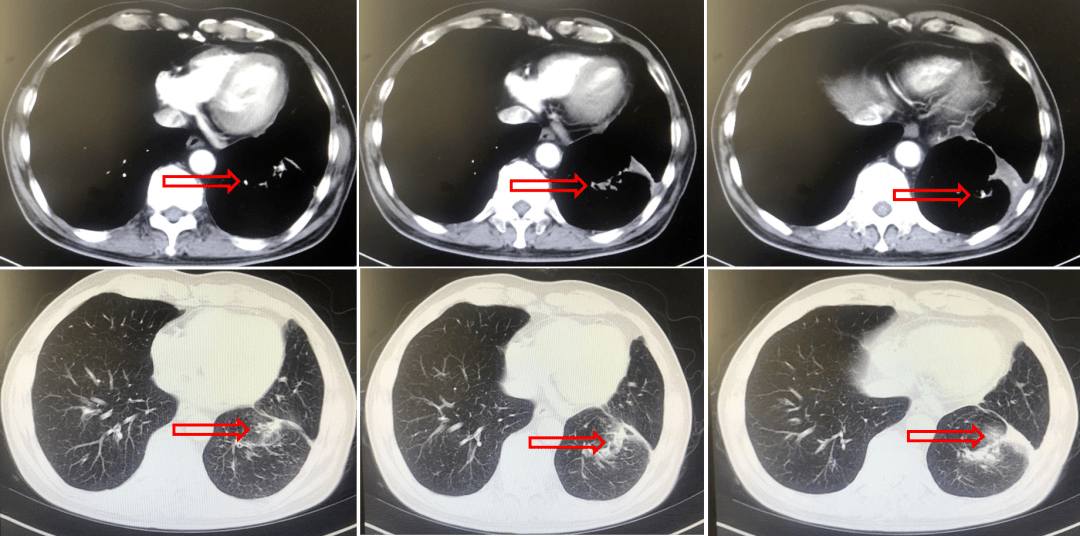

肺癌病例73岁晚期肺腺癌生存期接近4年

图片尺寸954x632